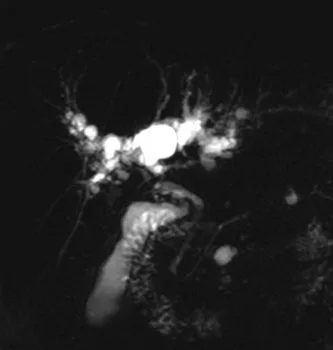

Figure 1. Patient exploré par bili-IRM pour une suspicion de migration lithiasique.

A. Cette coupe de bili-IRM 2D montre de multiples lithiases vésiculaires, ainsi qu’un calcul du bas cholédoque (tête de flèche).

B. Sur cette projection cholangiographique « MIP » issue d’une acquisition 3D en coupes fines, le calcul cholédocien est trop

petit au sein de cette VBP dilatée, et il n’est pas correctement visualisé. En cas de bili-IRM 3D, l’analyse de chacune des coupes

fines du volume est impérative. Ainsi, contrairement à la projection « MIP », la coupe fine passant par le cholédoque permet

de bien montrer le calcul (C)